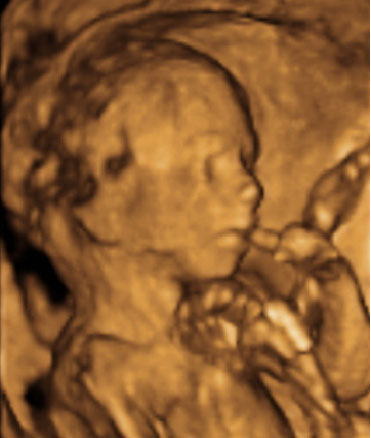

En la semana 20 de gestación, el aparato genital del feto ya es evidente, tanto en niñas como en niños con una ecografía en 4D. Los órganos genitales externos se formaron en la semana 12 de embarazo.

Cómo es el aparato genital femenino del feto en vídeo

En la imagen podemos apreciar un feto del sexo femenino con una edad gestacional de 20 semanas y 3 días.